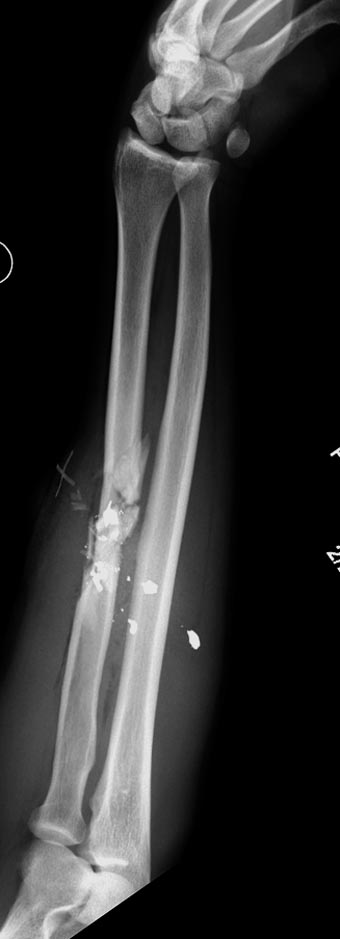

Здесь примеры: двоюродные братья с ранением предплечья, у одного локтевая, а у второго лучевая. В следующее утро локтевая фиксирована без обнажения фокуса травмы из небольших доступов, а второй из обычного волярного доступа. А клинический снимок из прошлых операций...